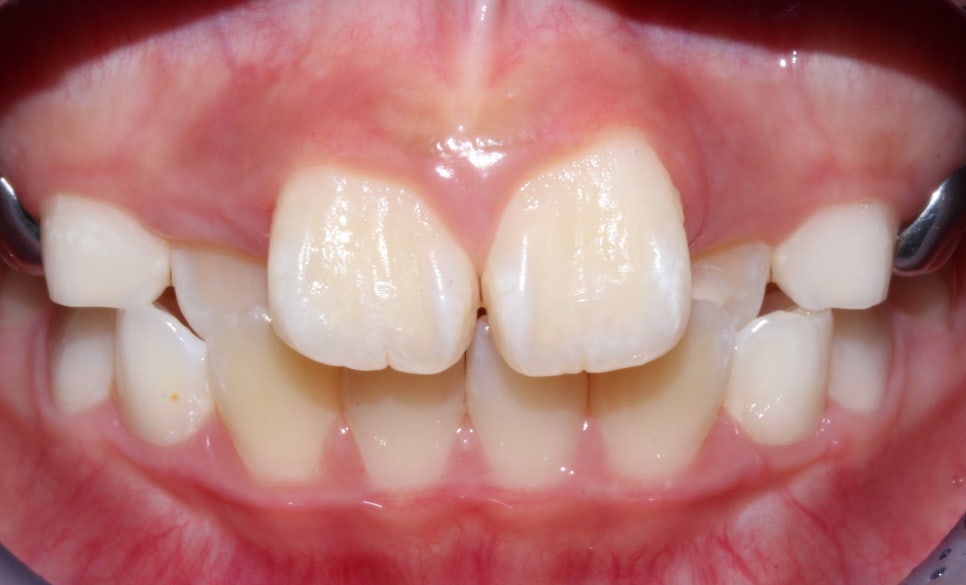

안 모의 변화 모습이에요.

상/하악 전치 모두 상당량이 후방으로 이동이 되었기

때문에 훨씬 심미적으로 변화가 되었어요.

<24개월 교정 완료 모습>

전체적으로 치아가 크게 개선이 되었어요.

저희뿐만 아니라 아이와 보호자 모두

교정 후의 차아 상태를 매우 만족해하셔서

기분이 좋았던 케이스에요